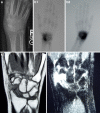

Osteoid osteoma of the scaphoid presenting with radiocarpal arthritis: a case report

A case of osteoid osteoma of the scaphoid presenting as painful monoarticular arthritis is presented. Degenerative arthritis, associated with osteoid osteoma of the carpus, has not been described. The implications for treatment are discussed.